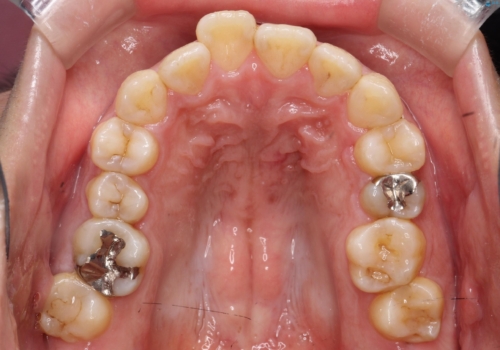

- 主訴:学生時代に矯正治療したが、後戻りしてしまった。上下前がのガタつきを治したい。

ワイヤー矯正(審美装置)非抜歯 治療期間:1年8か月

途中、大臼歯の遠心移動のためリンガルアーチを使用しています。